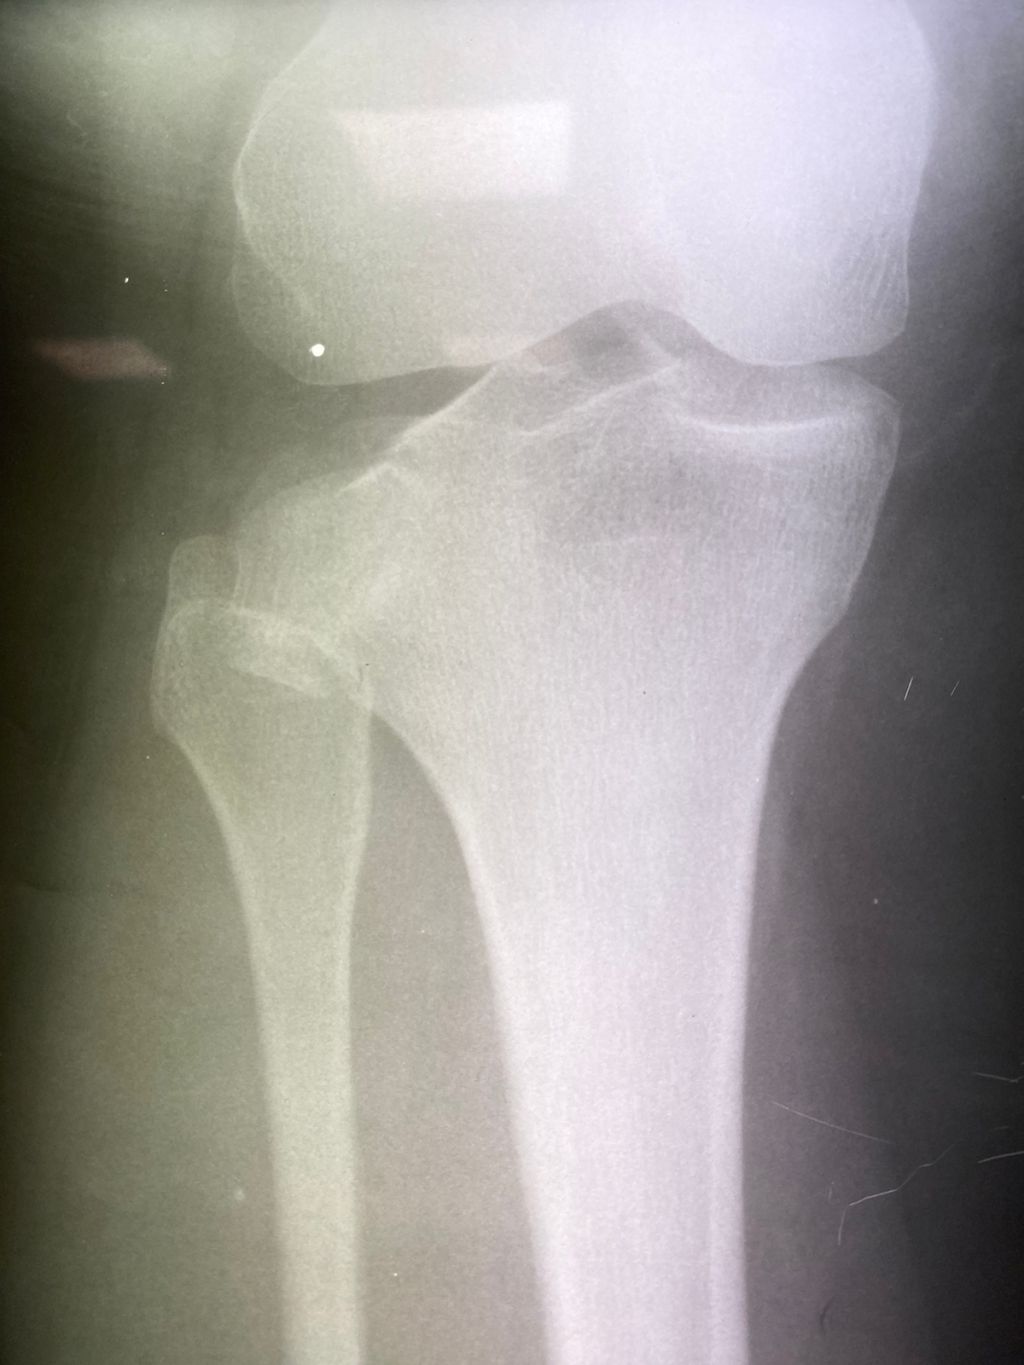

Получила травму колена в декабре 2022 года после дтп , по месту жительства меня оставили без какого-либо лечения , знакомые посоветовали обратиться к Николаю Николаевичу. Обратилась , оперативно просмотрел мои мрт/кт, сразу назначил день операции. Операция прошла замечательно, работа выполнена на 200% , очень рада , что встретила такого замечательного врача на... Ещё Получила травму колена в декабре 2022 года после дтп , по месту жительства меня оставили без какого-либо лечения , знакомые посоветовали обратиться к Николаю Николаевичу.

Обратилась , оперативно просмотрел мои мрт/кт, сразу назначил день операции.

Операция прошла замечательно, работа выполнена на 200% , очень рада , что встретила такого замечательного врача на своём пути.

С операции прошло уже почти полгода , не так давно начала ходить, сейчас прохожу реабилитацию.

Чувствую себя человеком) Большое спасибо Николаю Николаевичу за его работу, человечность и профессионализм!

Прикрепила фото До и после

Фото к отзыву о Гнелица Николай Николаевич Фото к отзыву о Гнелица Николай Николаевич